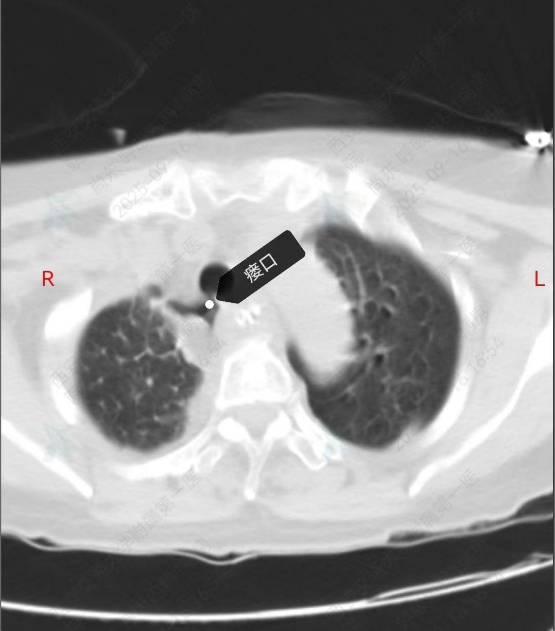

今年 9 月,赵阿姨有强烈的取出支架意愿,遂入住东院区呼吸与危重症医学科。入院后影像学提示其气管食管瘘口已基本愈合,具备取出支架的条件,但动态心电图仍显示频发室早,室早二联律,麻醉风险较高。为保障赵阿姨是安全,科室迅速启动多学科协作(MDT)机制,联合麻醉手术部、心血管内科、医学影像科、胸部外科专家进行全面讨论。经充分评估,最终制定手术方案:术前先行「左侧星状神经节阻滞术」改善心律失常,为后续麻醉及手术创造条件。

9 月 16 日,在东院区副院长、麻醉手术部主任高巍,副主任医师庞芸全程监护下,尚东主任带领团队成功为赵阿姨施行「硬质气管镜下硅酮支架取出术」。术中仔细清理支架周围感染灶及增生肉芽,完整取出留置两年之久的支架,并确认瘘口愈合良好,手术过程顺利,生命体征平稳。